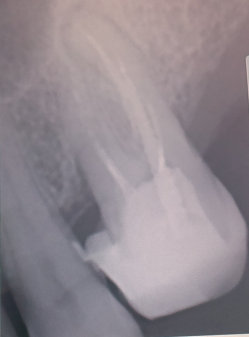

Мне 21 год. Год назад мне поставили химическую пломбу на 24 зуб. Пломба частично вывалилась, и как бы внутри зуба образовалась дырка, в которую постоянно попадала еда и гнила там. Через несколько месяцев я поставила новую пломбу, тоже химическую. Но возникла снова та же проблема.

Недавно я обращалась в несколько стоматологий. Мне сказали, что в зубе развивается кариес, и стенки его тонкие. Одни предлагали поставить штифт и новую светоотвердевающую пломбу. Другие говорили, что необходим штифт и коронка.

Естественно, в Вашем случае самый правильный и разумный метод — это протезирование.

Только штифт ставить не нужно. Необходимо восстановить коронковую часть зуба вкладкой, а затем установить коронку. В противном случае, установив штифт и пломбу, Вы рискуете и далее крошить стенки зуба, тем самым потеряете его. Обратитесь к частному стоматологу и протезируйтесь.